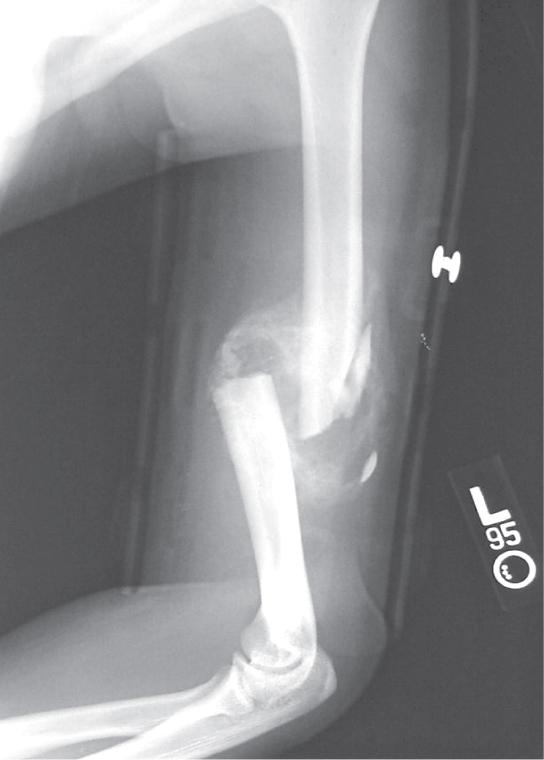

Photo shows an X-ray of a broken humerus—the bone in the upper arm.

Figure 29.22 After this bone is set, a callus will knit the two ends together. (credit: Bill Rhodes)